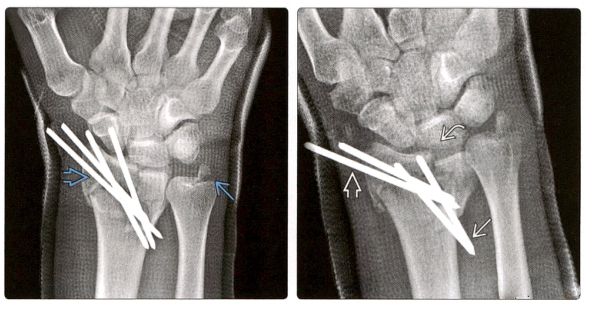

Лечение переломов основания средней фаланги чрескожным введением иглы

В случаях ортопедических переломов относительно распространены переломы основания средней фаланги, и Хинтрингер разд···

узнать больше